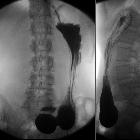

Hakenmagen bei einer Patientin mit Wilkie-Syndrom, also einer Kompression der Pars horizontalis des Duodenums zwischen Aorta und A. mesenterica superior. Wie abgemagert die Patientin war, sieht man am besten in der seitlichen Projektion.